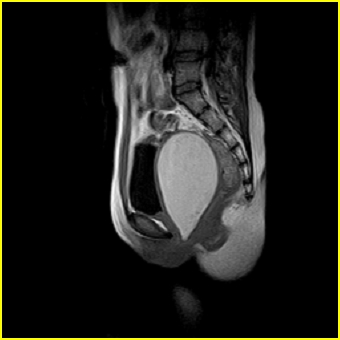

女、15岁、下腹疼痛2天,排尿困难1天。查体:处女膜闭锁,距处女膜约4至5cm处扪及一约5cm直径的圆形包块,张力较高,触痛明显、欠活动。b超提示子宫增大伴宫内增强回声团。

更正影像意见:阴道积血。

处女膜闭锁,阴道积血,子宫积血.

阴道积血,子宫积血.

子宫及阴道积血。

处女膜闭锁,伴子宫及阴道积血.